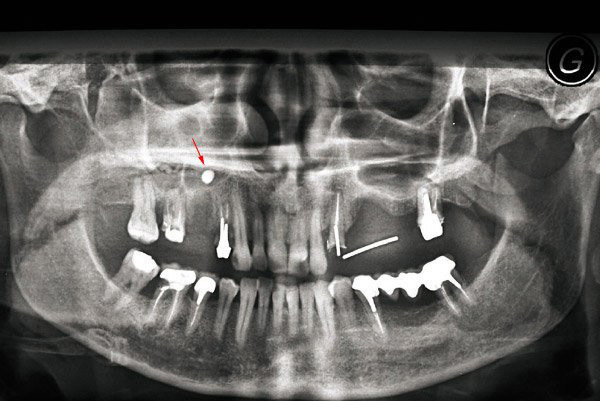

Dépassement de pâte dentaire inter-sinusien en regard de l’alvéole déshabitée de 15 (flèche). Les apex des molaires et des prémolaires ayant des rapports étroits avec les sinus maxillaires, ces dents peuvent être en cause dans la survenue des sinusites maxillaires, en règle générale chroniques et unilatérales. À noter que l’aspergillose sinusienne est une complication classique liée au dépassement de pâte d’obturation canalaire en intra-sinusien lors d’un traitement endodontique.